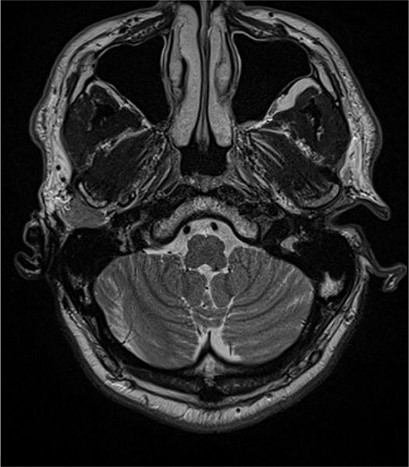

A 56- year old male was presented in the Outpatient Department of Otolaryngology Clinic with main complaint of complete aural atresia of the right ear. The clinical examination revealed that there was no external auditory canal in the right ear (Fig. 1) and hearing loss was altered (Fig. 2). There was no symptomatology in the left ear and the anatomic structures were completely normal. Blood test was normal, and there were no other medical issues from the personal history. The computed tomography (CT) scan and mainly the magnetic resonance imaging (MRI) of the temporal bone revealed no mastoid air cells and no external auditory canal and auricle (Figs 3 and 4). There was a normal anatomy of the internal auditory canal on both sides. Left side of the external auditory canal was normal. Diagnosis of this anatomical malformation was compatible with congenital atresia of the external auditory canal on the right temporal region. The patient decided to proceed to surgery many years after the first diagnosis. Some weeks ago, canalplasty and tympanoplasty were performed by our surgery team. During surgery, a graft has been obtained in order to formate the covering of the new canal. The incision was made behind the ear at the level of temporal bone, and the graft needed is removed from the temporal fascia and inserted as covering of the new canal. The aim is to create a new anatomic pathway resembling a normal external acoustic canal by drilling the atretic bone and removing the present tissue (Figs 5 and 6).

Preoperative examination includes blood tests, audiogram and mostly imagistic examination. CT scan and MRI are necessary for evaluating the surrounding anatomical structures, the deformities and are quite helpful in the surgery plan. In this present case, the imagistic examination revealed unilateral mastoiditis, right atresia of the external acoustic canal and normal anatomy of the other unaffected side. According to Jahrsdoerfer grading system [4], the surgical success can be based on some clinical features regarding the profile of candidates for operation. Based on CT scan and identifying the anatomical structure, such as oval window open, middle ear space, facial nerve, malleus incus complex, mastoid pneumatization, incus-stapes connection, round window and external ear, a score is calculated, and if it is >7/10, surgical success is predicted [5, 6]. The treatment of this anatomical malformation is only surgical repair, resulting in the formation of a new bony canal resembling the external auditory one, by drilling the atretic bone and widening the closed space by removing the stenotic tissue [7]. Repair of the stenotic canal can be succeeded by anterior or posterior approach. In our case, anterior approach has been chosen. The mastoid antrum approach as and operative technique is quite reliable [8]. Removal of the stenotic and fibrotic abnormal tissue requires drilling of the atretic plate over the temporal line behind the glenoid fossa. The drilling stops at the borders of the anterior epitympanium. When the new canal is formatted, it is covered by graft. The goal is to maintain the width of new aural canal. The reconstructed auricle requires use of porous polyethylene material (MedPor) or autologous rib cartilage [8, 9]. In our patient, the auricle was repaired some years ago before the surgical repair of the atretic external auditory canal.